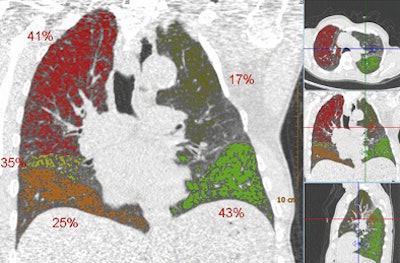

| Above, images from the expiration scan of a 65-year-old man with GOLD stage 3. The image shows increased density in some areas, common in expiration scans, but also regions that remain dark and are indicative of air trapping. Below, the overlay images from a single coronal section show that the left upper lobe is normal, while two lobes had emphysema and two had air trapping, indicating mixed-phenotype COPD. |

![]() |